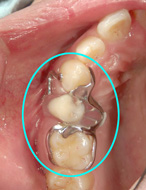

患者様と相談をした結果、将来を見越して一時的に入れ歯を装着=写真左=してもらうことにしました。入れ歯なら、健全な白い歯を2本、大きく削る必要がないからです。